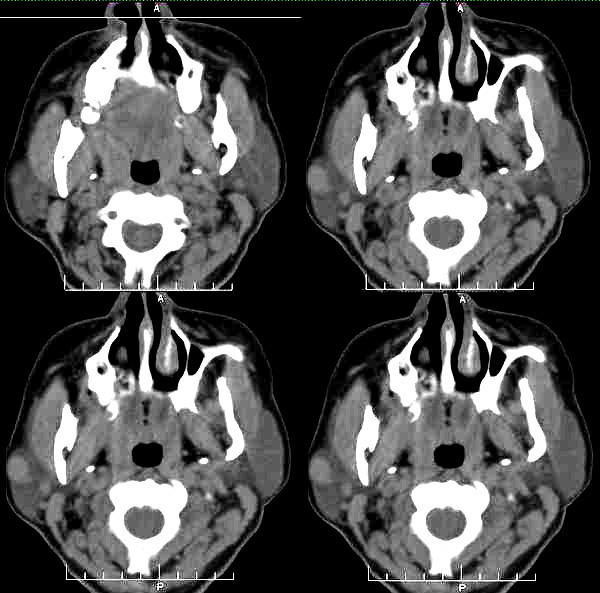

标题: CT2109:右腮腺区肿物

女35岁,右腮腺区肿物一年余

对不起,图像的窗宽窗位不合适,腮腺的组织不清楚,层次不分明,无法观察,能否再上传图像?。

病史长,病灶光滑锐利、密度均匀,未见坏死,右侧腮腺浅叶的混合瘤首先考虑

右侧腮腺浅叶圆形稍高密度影,边缘光整,考虑腮腺囊腺淋巴瘤。